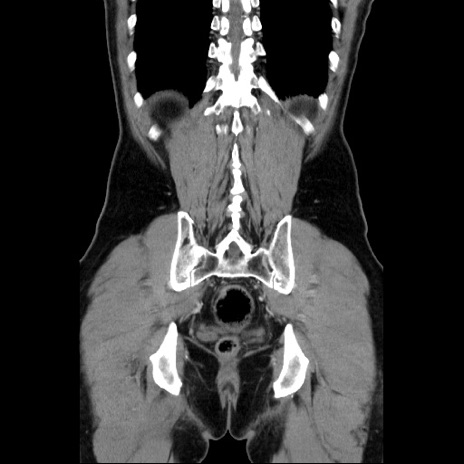

横断像

【症例】60歳代 男性

【主訴】右鼠径部膨隆

【現病歴】1年程前より右鼠径部膨隆あり。自己にて還納可能だったため放置していた。3時間前より右鼠径部の脱出を認め、還納困難となり受診。

【既往歴】高血圧

【身体所見】右鼠径部に小児頭大の膨隆あり。弾性硬であり、用手還納は困難。左鼠径部にも膨隆を認める。脱出はなし。